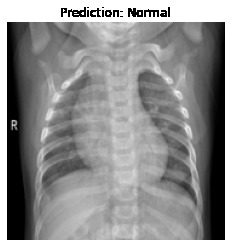

Currently, there is an urgent need for efficient tools to assess the diagnosis of COVID-19 patients. In this project, we propose a constructive solution for detecting and labeling infected tissues on CT lung images of such patients. To cut down false positives our model is trained on 4 types of lung CT images : COVID, Viral Pneumonia, Lung Opacity and normal images to get the best possible results with highest accuracy.

We learned that COVID-19 can be succesfully detected through LUNG-CT images instead of tedious tests like Reverse transcription polymerase chain reaction (RT-PCR) which takes almost 5 hours and Rapid detection tests which has a low accuracy.